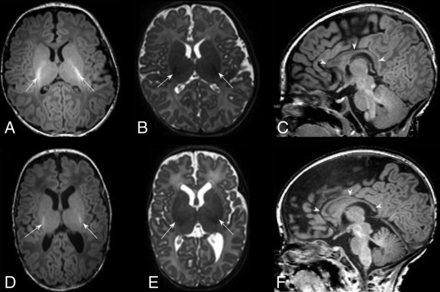

HPI. T2-weighted MR images through the mid (A) and low (B) basal ganglia level in an infant born at 29 weeks and imaged at 44 + 6 weeks. There is right-sided HPI with formation of a porencephalic cyst lined with low signal intensity consistent with previous hemorrhage (arrow, A), a paucity of low T2 signal myelin in the right PLIC compared with the left (arrowheads, A), and ipsilateral basal ganglia and thalamic atrophy (arrowheads, B). This infant had a motor impairment at 20 months.

PVL. T2-weighted images in the axial plane at the level of the basal ganglia (A) and the corona radiata (B) of an infant born at 29 + 5 weeks’ and imaged at 39 + 1 weeks’ PMA. There are cysts in the periventricular white matter bilaterally (arrows, A and B) accompanied by an absence of high-T1/low-T2 signal in the PLIC, denoting an absence of myelin (arrowheads, A). More commonly, cysts are not seen at term age. T2- (C) and T1-weighted (D) images in the axial plane at the level of the basal ganglia and PLIC in an infant born at 29 + 3 weeks’ and imaged at 40 + 2 weeks’ PMA show mild angulation and dilation of the posterior horns of the lateral ventricles and high-T1/low-T2 signal in the periventricular white matter (arrows, C and D), secondary to white matter volume loss (note that the sulci approximate the ventricular surface), similarly accompanied by a lack of myelin in the PLIC (arrowheads, C and D), features that are typical of noncystic PVL.